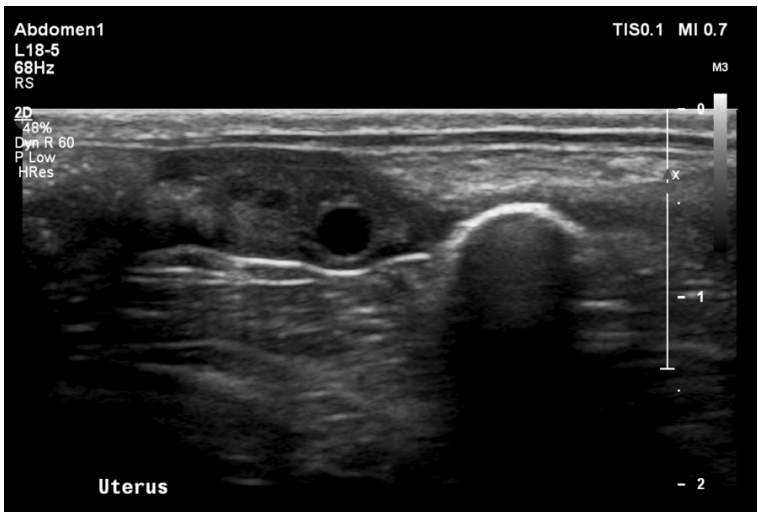

What is shown in this image?

A

normal non-gravid uterus in an intact female dog